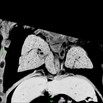

Caption Play MovieSerial 2D EFIC image stack in the coronal plane of 2187-006-1 (E15.5) shows biventricular hypertrophy